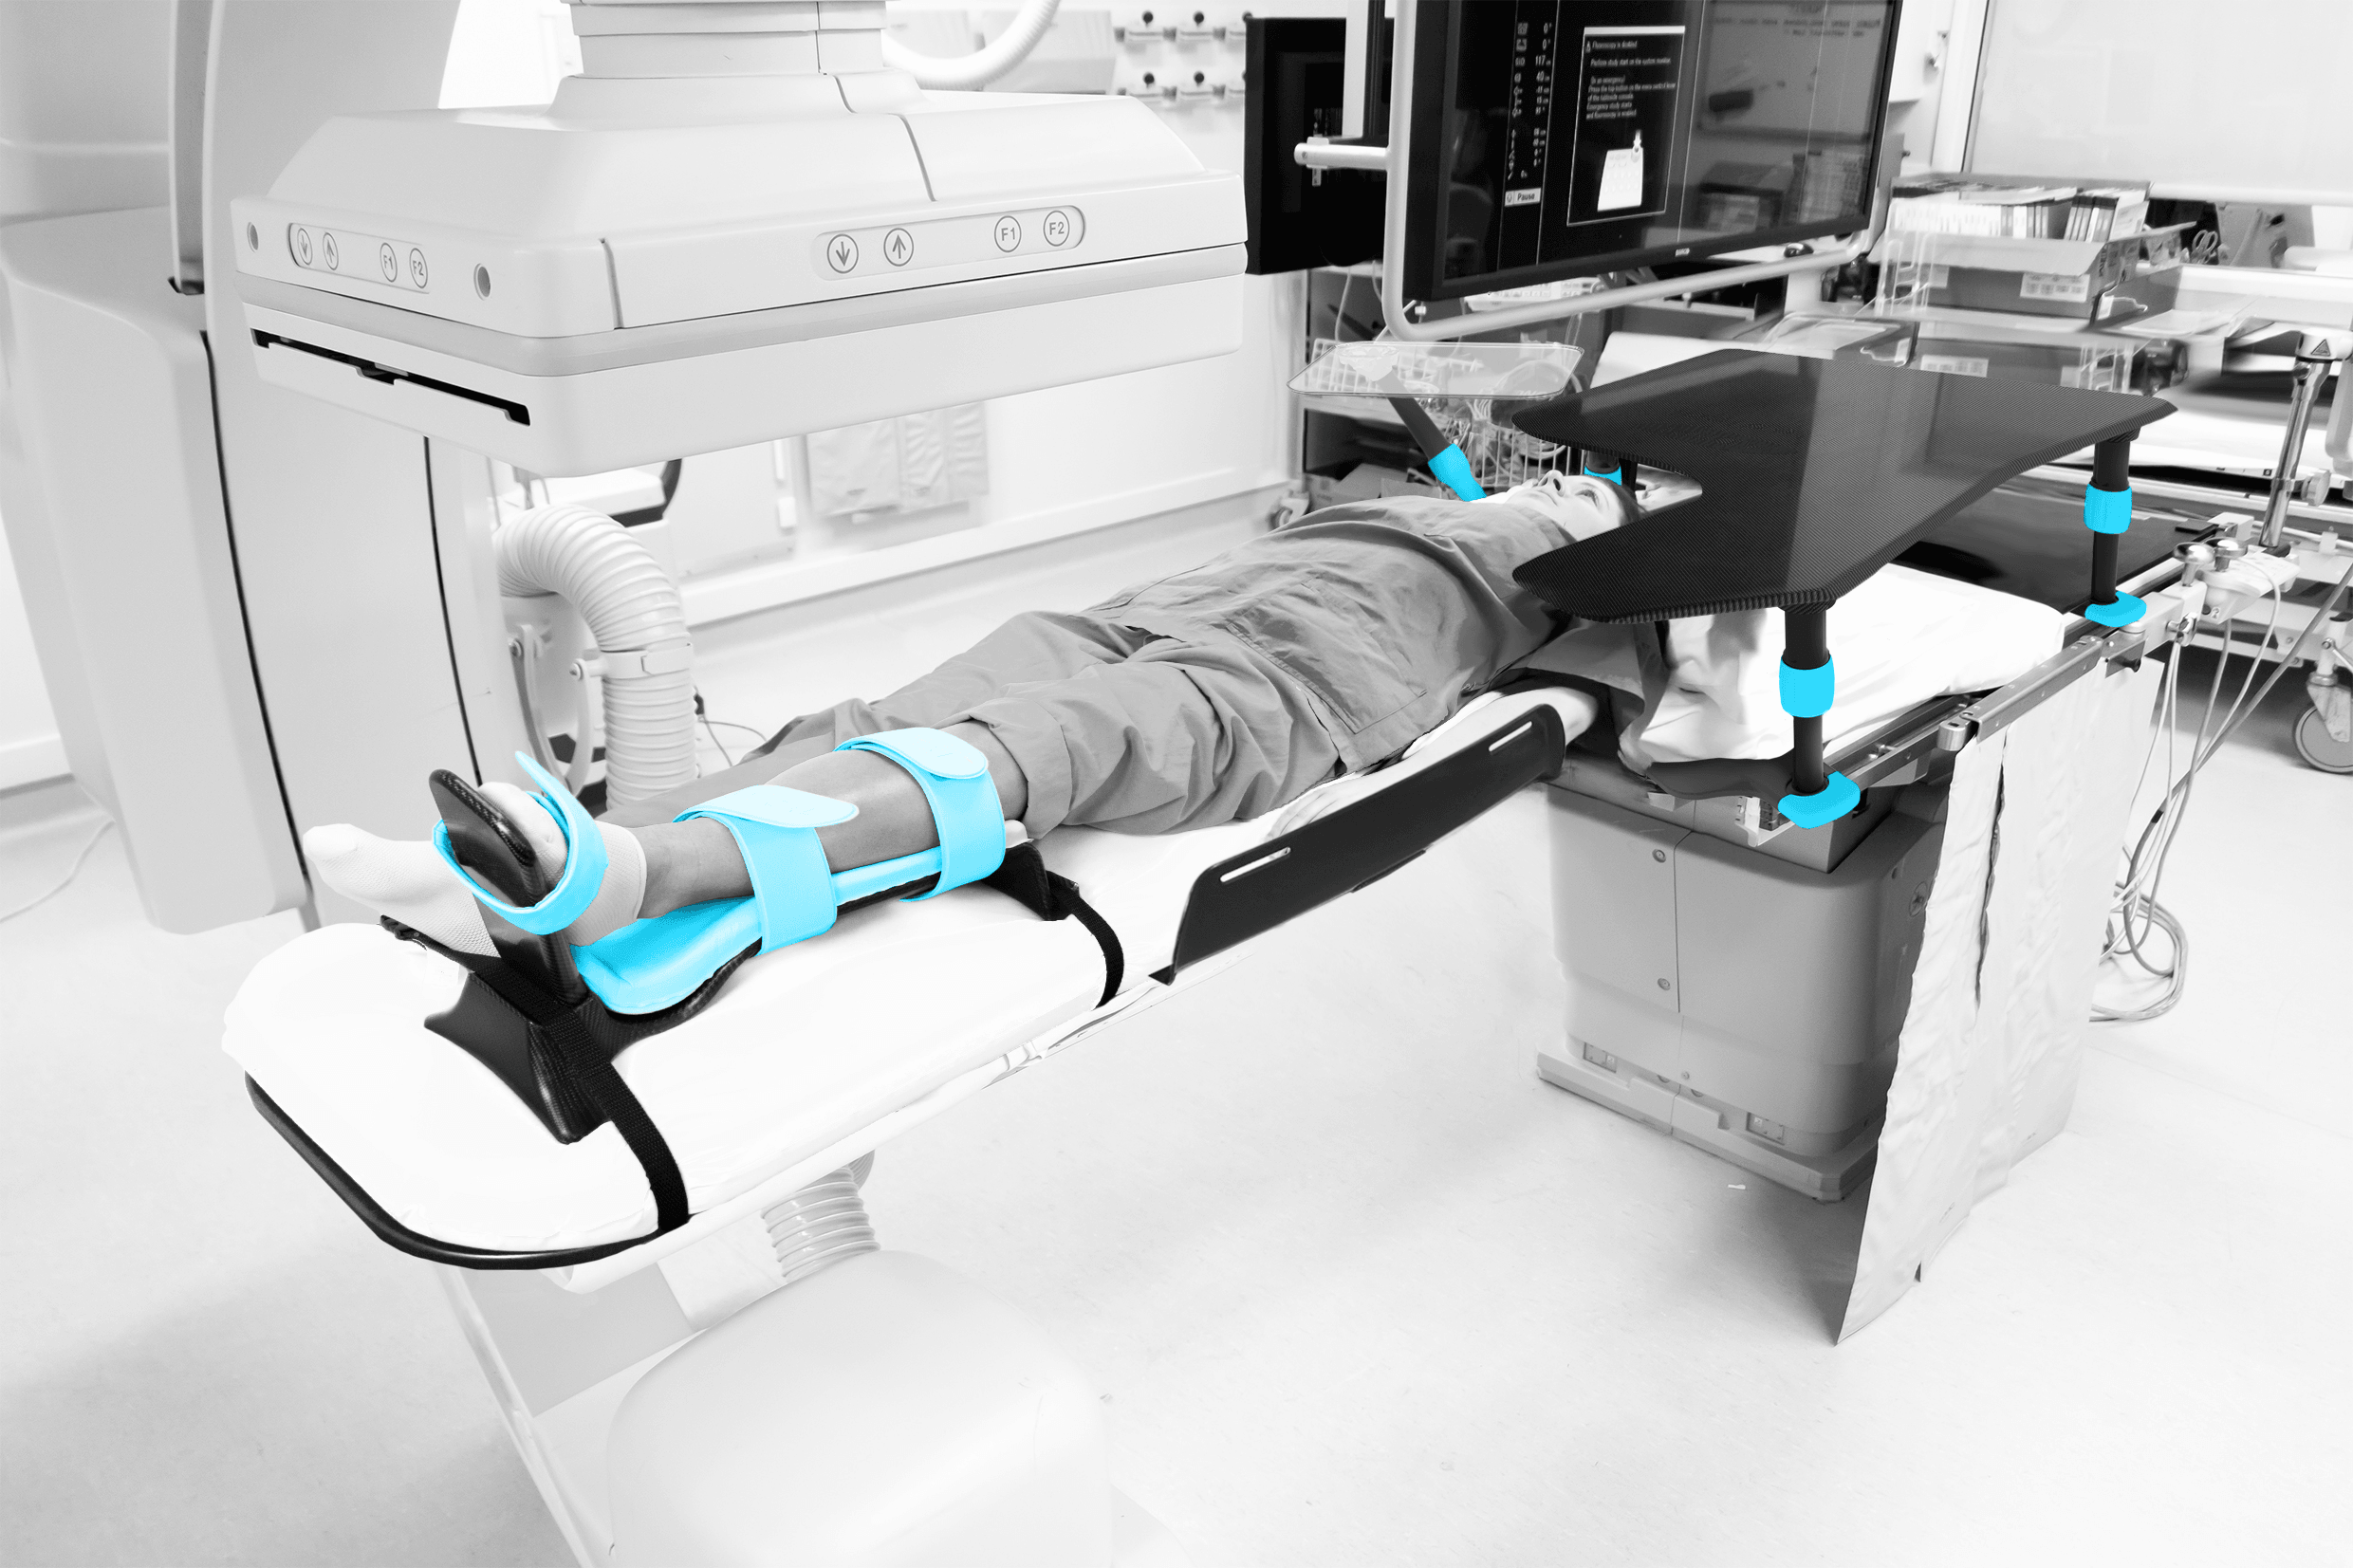

We design medical devices that support patient positioning, clinician ergonomics and procedural workflow in interventional radiology, cardiology and neuroradiology. Devices also available for otology, rhinology and sterilisation.

Interventional RadiologyInterventional CardiologyInterventional NeuroradiologyPeripheral InterventionGeneral Surgical

Since 2003, we’ve been designing and manufacturing purpose-built medical devices that support clinicians, simplify workflow, and enhance patient care.

We focus on quality, performance and reliability to help support better outcomes for both patients and healthcare professionals. Our design engineers interact early with clinicians to ensure our products integrate seamlessly with existing workflows.